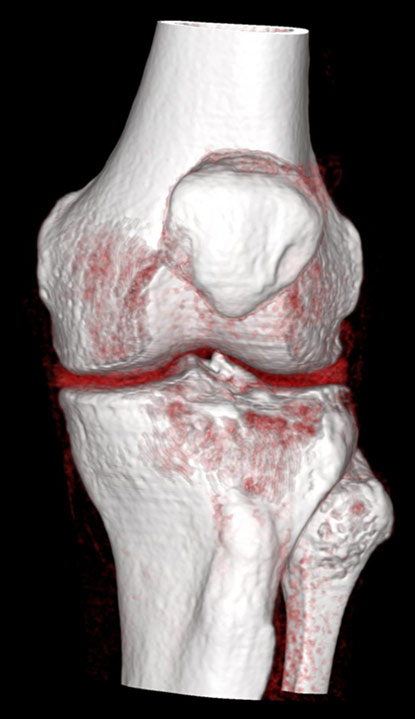

Imaginile cu parametri de părți moi (“kernel” dedicat părților moi) sunt de obicei cu contururi mai line, mai “smooth”, cu “netezirea” artificială a micilor detalii și permit reconstrucții 3D foarte plăcute ochiului, cu aspect anatomic.

Reconstrucții tridimensionale